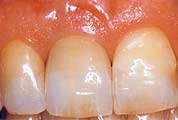

Der Natur am nächsten ist es, die naturgegebene Situation wieder herzustellen: Mit einer Implantatkrone wird die sichtbare Zahnkrone und die unsichtbare Zahnwurzel ersetzt - so, als wäre es Ihr eigener Zahn. Sichern Sie sich langfristig ein Höchstmaß an sicherem Auftreten und Komfort!

Wann machen Implantate Sinn?

Einzelzahnersatz

Gesunde Nachbarzähne müssen nicht beschliffen werden. Eine

unauffällige und natürliche Lösung. Anspruchsvoll in

der Ästhetik und langfristig im Nutzen.